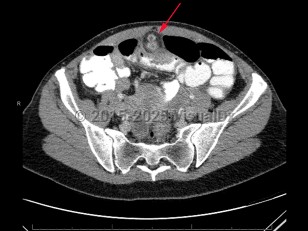

Imaging Studies image of Meckel diverticulum - imageId=7879679. Click to open in gallery.  caption: '<span>CT scan of abdomen and pelvis demonstrating enhancing nodular focus extending from ileum, which was pathology-proven Meckel diverticulitis.</span>'

CT scan of abdomen and pelvis demonstrating enhancing nodular focus extending from ileum, which was pathology-proven Meckel diverticulitis.